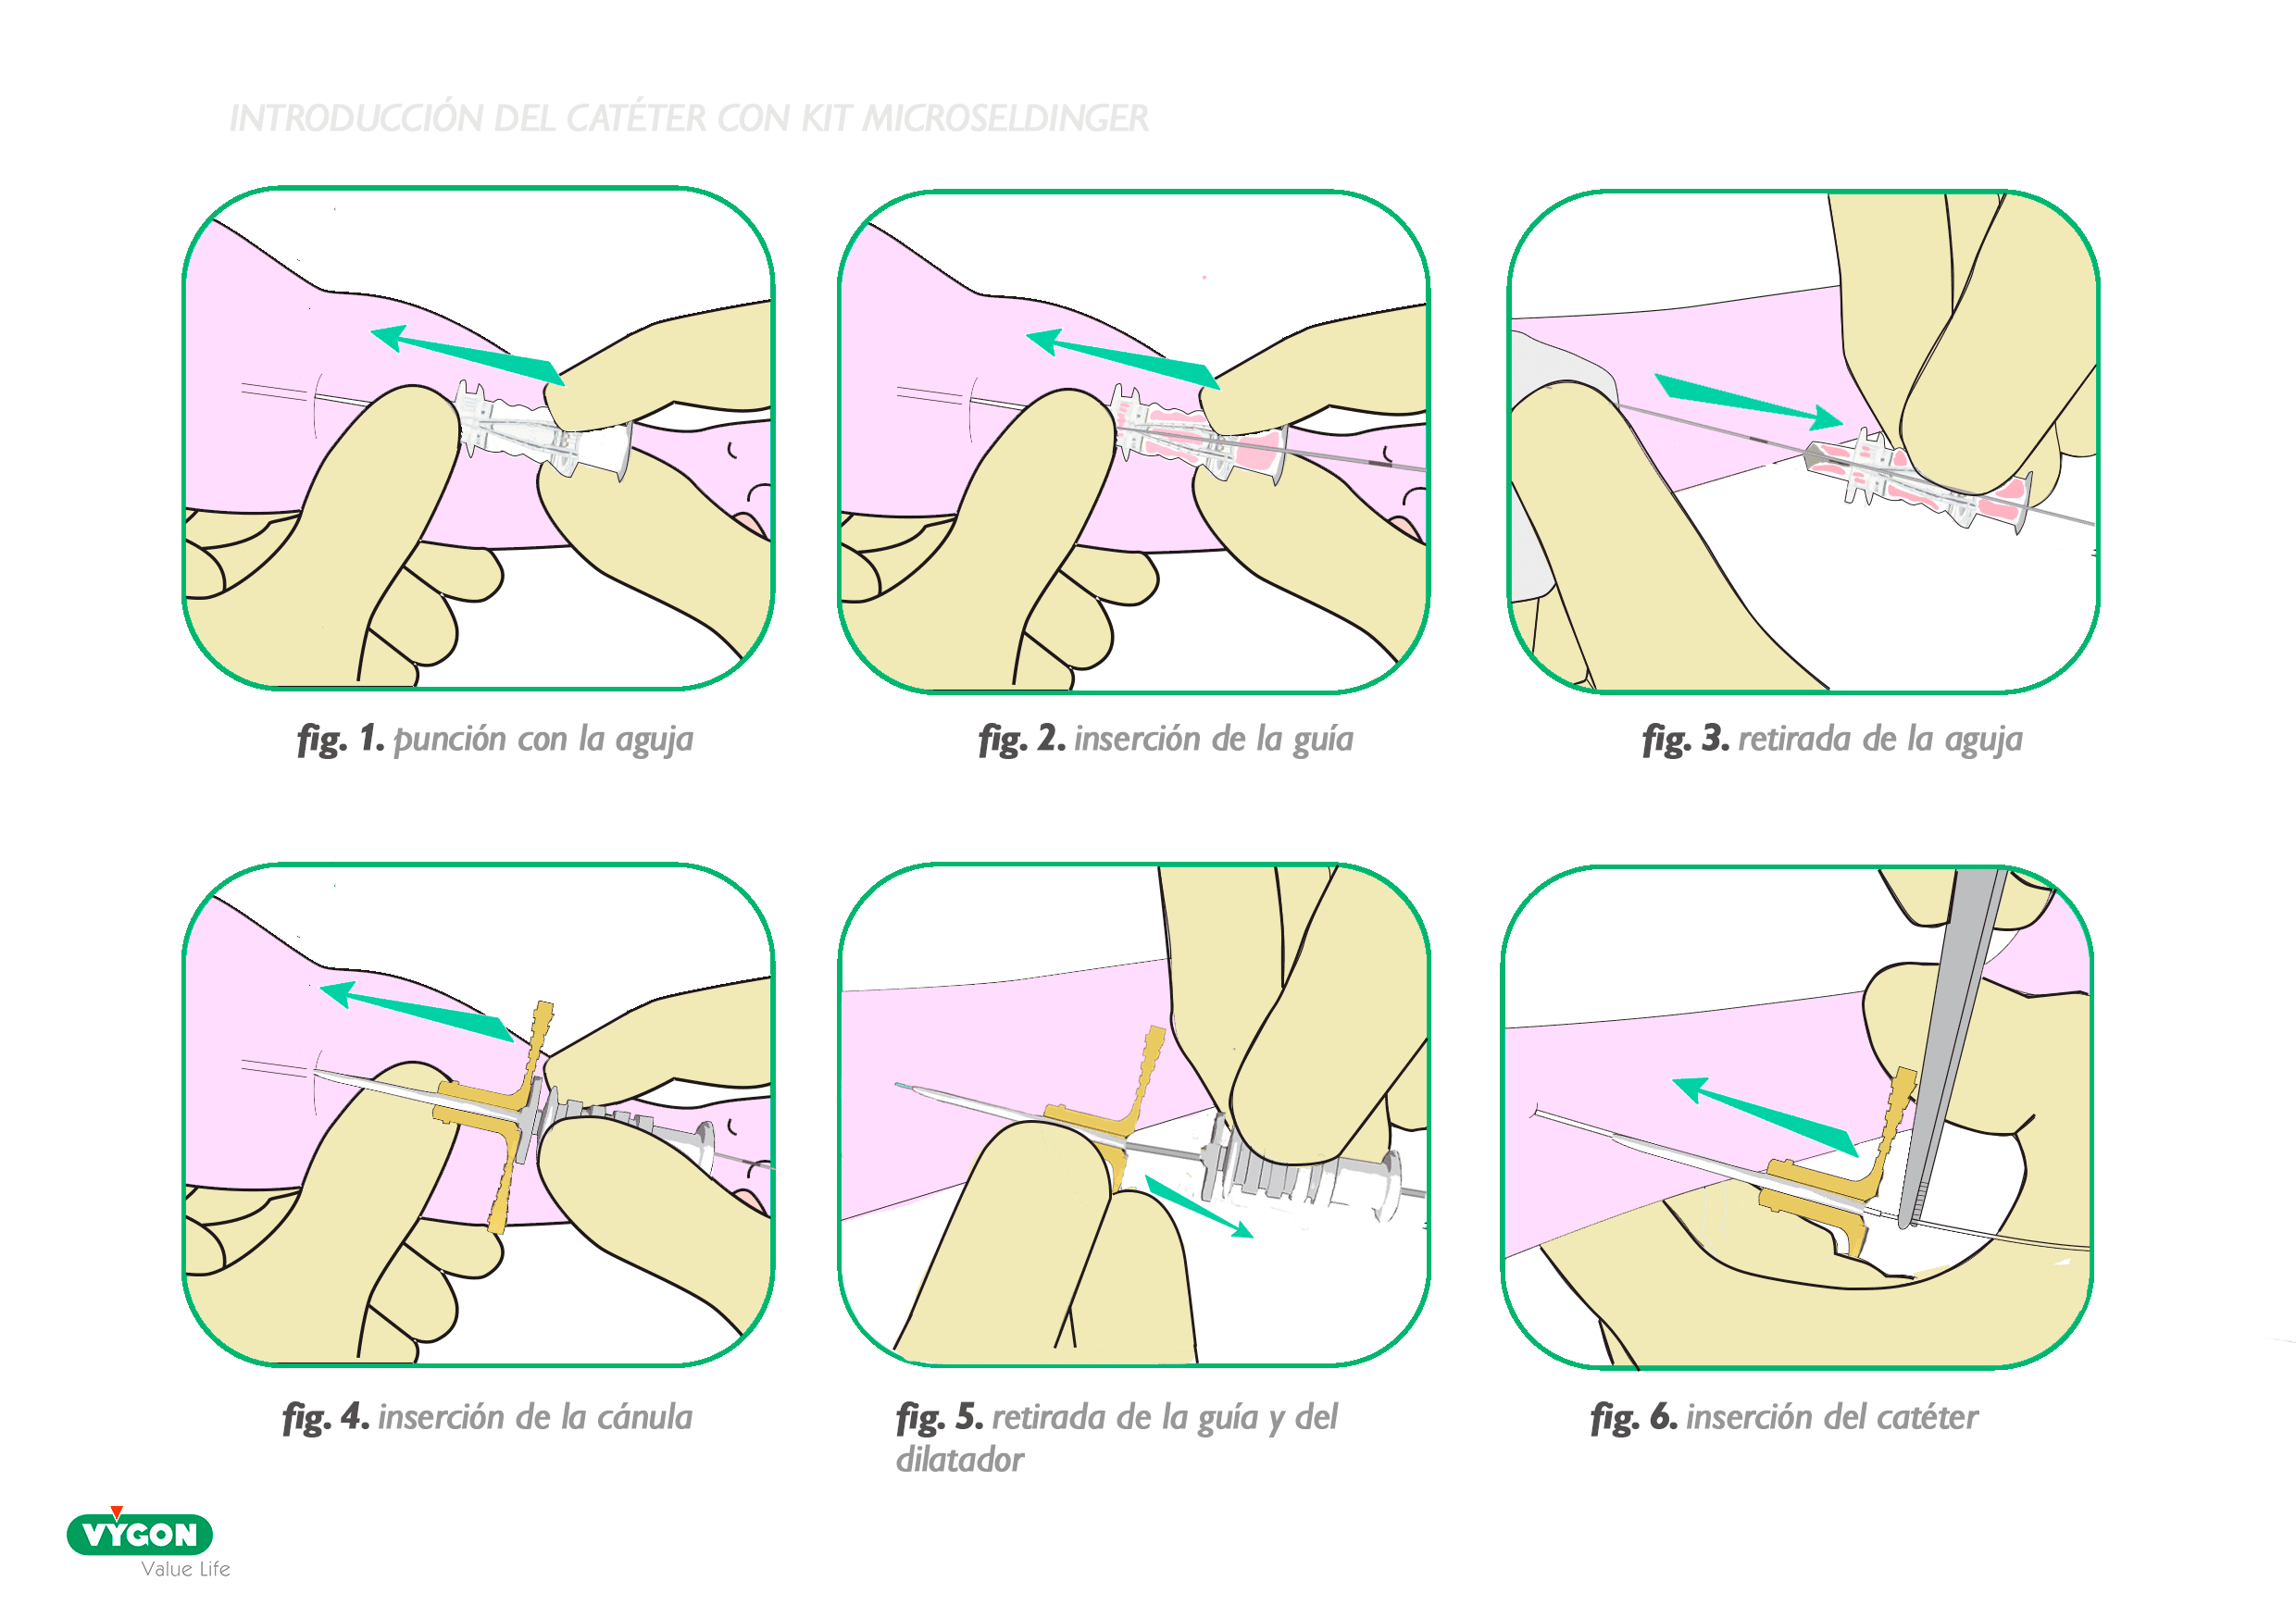

KIT MICROSELDINGER

- una aguja de 24G y 19mm

- cánula pelable de 20G y 18mm

- guía de nitinol de 0.3mm en su extremidad roma (menos en su longitud)

VENTAJAS

- Reducción máxima de la invasividad durante la inserción:

- La punción es muy fina gracias a la aguja de 24G

- La canalización de la vena se hace con la guía flexible (riesgo mínimo de transfixión comparando con una canalización hecho con un introductor de otro tipo)

- Evita el trauma endotelial: la guía lleva una bola pequeña en su extremidad

- El microintroductor tiene una punta perfilada para permitir una introducción suave

- Minimiza el riesgo de pérdida de la vena: la estabilización de la guía no es clave como con la aguja ya que:

- Está canalizado sobre más recorrido venoso

- Es flexible y no punzante

- Permite canalizar venas de muy difícil acceso (por agotamiento del capital venoso y/o por riesgo de colapso) y venas más profundas (no visibles)

INCONVENIENTES

- Es el sistema de introducción que mayor curva de aprendizaje presenta al ser muy diferente a los introductores usados habitualmente en neonatología (varios componentes y pasos)